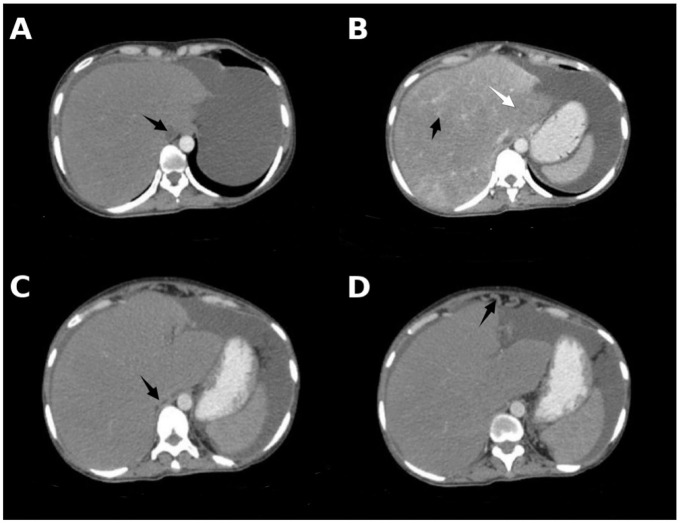

Abstract Image